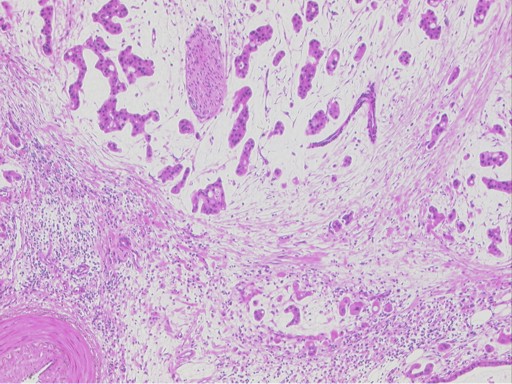

The surgical specimen contained a 10 cm multilocular cystic mass with several papillary projections in the tail of the pancreas and a 6 cm solid area in the head of the pancreas which caused dilatation of the main pancreatic duct (Figure 5). Microscopic features of the pancreatic tumor showed a particularly complex architecture with arborizing papillae as well as invasive areas characterized by small nests of cells with extracellular mucin accumulation. The tumor cells in both components showed abundant granular eosinophilic cytoplasm, a characteristic feature of this neoplasm due to numerous mitochondria (Figure 6).

Figure 6. Microscopic features of the pancreatic tumor showing a particularly complex architecture with arborizing papillae as well as invasive areas characterized by small nests of cells with extracellular mucin accumulation. Invasion front composed of tumor cells with abundant eosinophilic cytoplasm surrounded by abundant mucin. A perineural invasion in the tumor area can also be observed as can a peritumoral desmoplastic stromal reaction. |

The neoplastic cells expressed abundant and diffuse hepatocyte paraffin-1 and cytokeratin 19 whereas the expression of CEA, MUC1, MUC2 and synaptophysin was focal. No expression of CDX2 or chromogranin was observed.

Of the 21 regional lymph nodes examined, we found a metastatic process in only two of them.